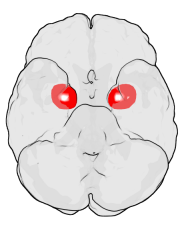

사회성, 얼굴 표정, 그리고 편도체

편도체는 사회적 신호를 해석하는 데에도 중요한 역할을 합니다. Adolphs et al.(1994)은 편도체 손상 환자가 두려움이 담긴 얼굴 표정을 인식하지 못한다는 사실을 보고했습니다. Sun et al.(2023)은 Translational Psychiatry에서, 모호한 표정을 해석할 때 편도체와 전전두엽의 연결성이 핵심적이라고 밝혔습니다. 또 Bickart et al.(2011)은 편도체의 부피가 클수록 더 많은 사회적 관계를 유지한다는 사실을 확인했습니다. 이는 편도체가 단순히 공포를 넘어서, 사회적 유대와 감정 이해에까지 영향을 미친다는 점을 보여줍니다.